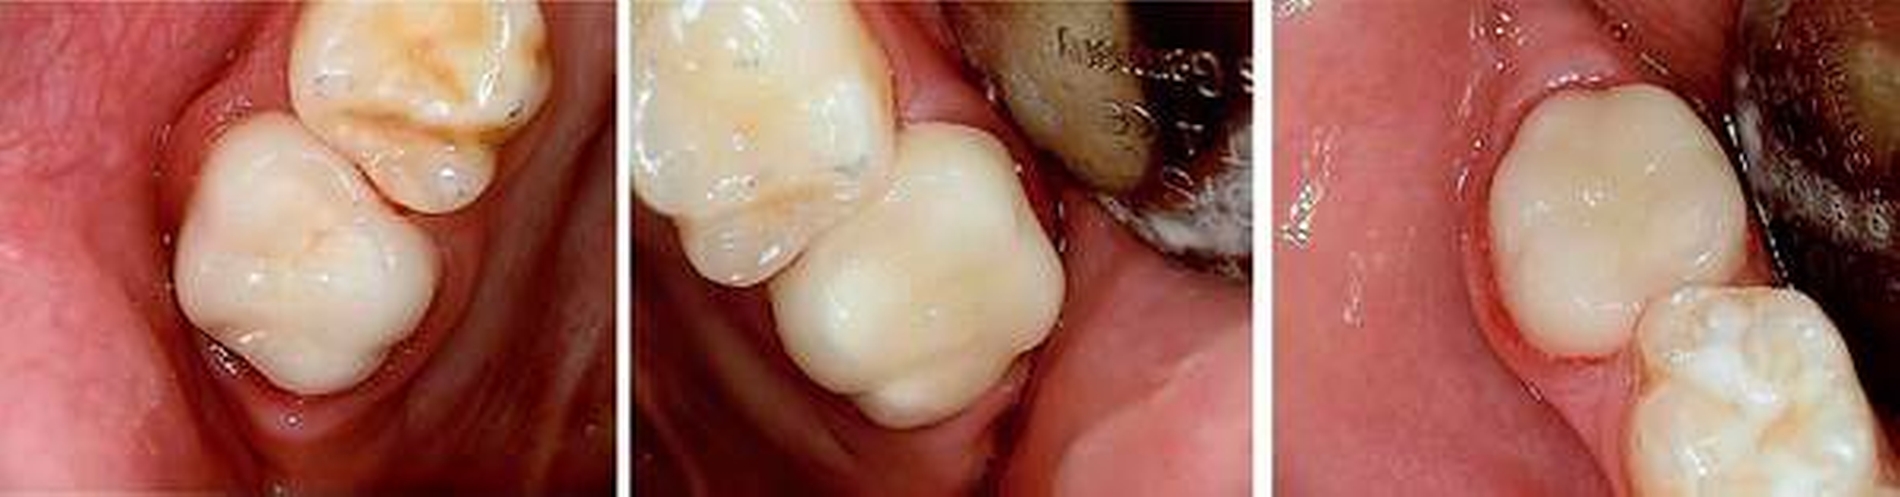

Therapie:Nach Befundaufnahme und Besprechung mit den Eltern und dem hinzugezogenen Kieferorthopäden wurden alle Behandlungsalternativen ausführlich besprochen. Aufgrund der Vorerkrankung und der täglichen Belastung des Kindes entschieden sich die Eltern für eine möglichst schnelle und langfristige Lösung. Außerdem sollte die Ästhetik, also die Zahnfarbe, auch im Seitenzahnbereich, mit berücksichtigt werden.

Gemeinsam wurde entschieden, dass die nicht so schmerzempfindlichen Frontzähne zunächst so belassen und gegebenenfalls später, wenn die optimale Zahnstellung erreicht ist, mit Füllungen oder Veneers versorgt werden. Die Zähne 16, 26 und 46 sollten mit Keramikkronen versorgt werden (Abbildungen 11 bis 13). Der weniger stark betroffene Zahn 36 sollte, wenn möglich, mit einer Kunststofffüllung versorgt werden. Eine mögliche spätere Extraktionstherapie je nach Engstand oder auch anstelle einer gegebenenfalls notwendigen Weisheitszahnentfernung wurde abgeklärt. Hinzu kam eine Füllungstherapie für die Zähne 64, 74 und 84. Der Zahn 54 wurde extrahiert, da die Wurzelresorption für eine Pulpotomie schon zu fortgeschritten war.

Aufgrund der Vorbelastung der jungen Patientin und der starken Schmerzempfindlichkeit wurde die Behandlung in ITN durchgeführt. Das Zementieren der Keramikkronen (mit Oxidkeramik/e.max) konnte wiederum in der Praxis durchgeführt werden (Abbildungen 14 bis 16), da die Patientin großes Vertrauen zeigte und sich ihren Wunsch von schmerzfreien Zähnen erfüllen wollte. Ansonsten wäre optional noch zusätzlich zur Lokalanästhesie die Lachgasbehandlung anstelle eines zweiten kurzen ITN-Termins möglich gewesen.

Prognose:Auch hier ist aufgrund der guten Compliance der Patientin und der Eltern der weitere notwendige Behandlungsverlauf als positiv einzuschätzen. Bei entsprechender Mundhygiene und Intensivprophylaxe kann eine weitere Behandlung sicherlich längerfristig vermieden werden. Sollte sich doch ein durch Extraktion therapiebedürftiger Engstand ergeben, so kann in ein paar Jahren immer noch entschieden werden, ob es sinnvoller ist, die Sechsjahrmolaren zu entfernen (mit folgender Multibandtherapie) oder ob die Weisheitszahnentfernung ausreichend ist. Aufgrund der verzögerten dentalen Entwicklung kann in diesem Fall aus kieferorthopädischer Sicht noch abgewartet werden.